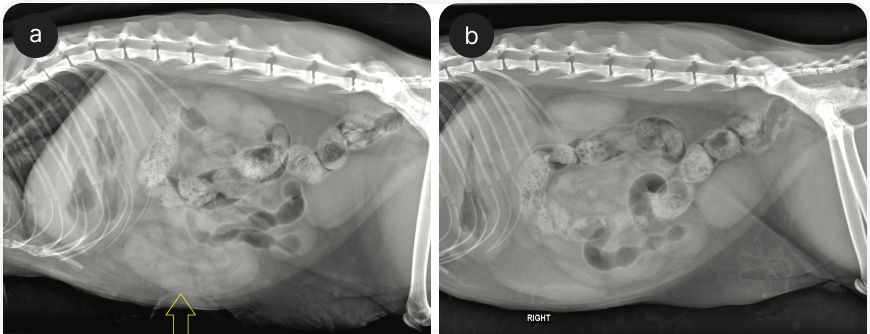

Пальпация брюшной полости без признаков отклонений не позволяет полностью исключить заболевания; даже при легкой форме заболевания проводят рентгенографию органов брюшной полости и в случае необходимости — хирургическое лечение. Если при рентгенографии не выявляют инородное тело (например, оно нерентгеноконтрастное), нужно оценить его непрямые симптомы, такие как центральное «скопление» петель кишечника (Рисунок 1) или аномальные пузырьки кишечного газа в форме полумесяца или слезы (5). Наличие так называемого симптома гравийных камешков указывает на хроническую кишечную непроходимость (Рисунок 2).

Инородные тела в кишечнике, помимо линейных, обычно вызывают его полную непроходимость с расширением краниально расположенных петель тонкой кишки (5). Аналогичным образом, в некоторых случаях хронических заболеваний ЖКТ (особенно у молодых кошек) может наблюдаться хроническая/динамическая инвагинация кишечника без явного расширения кишечных петель. Очень важно получить две, а лучше три рентгенограммы органов брюшной полости (лево- и правосторонние боковые и в ортогональной проекции), поскольку важнейшие нарушения могут выявляться только на одном снимке (Рисунок 3).